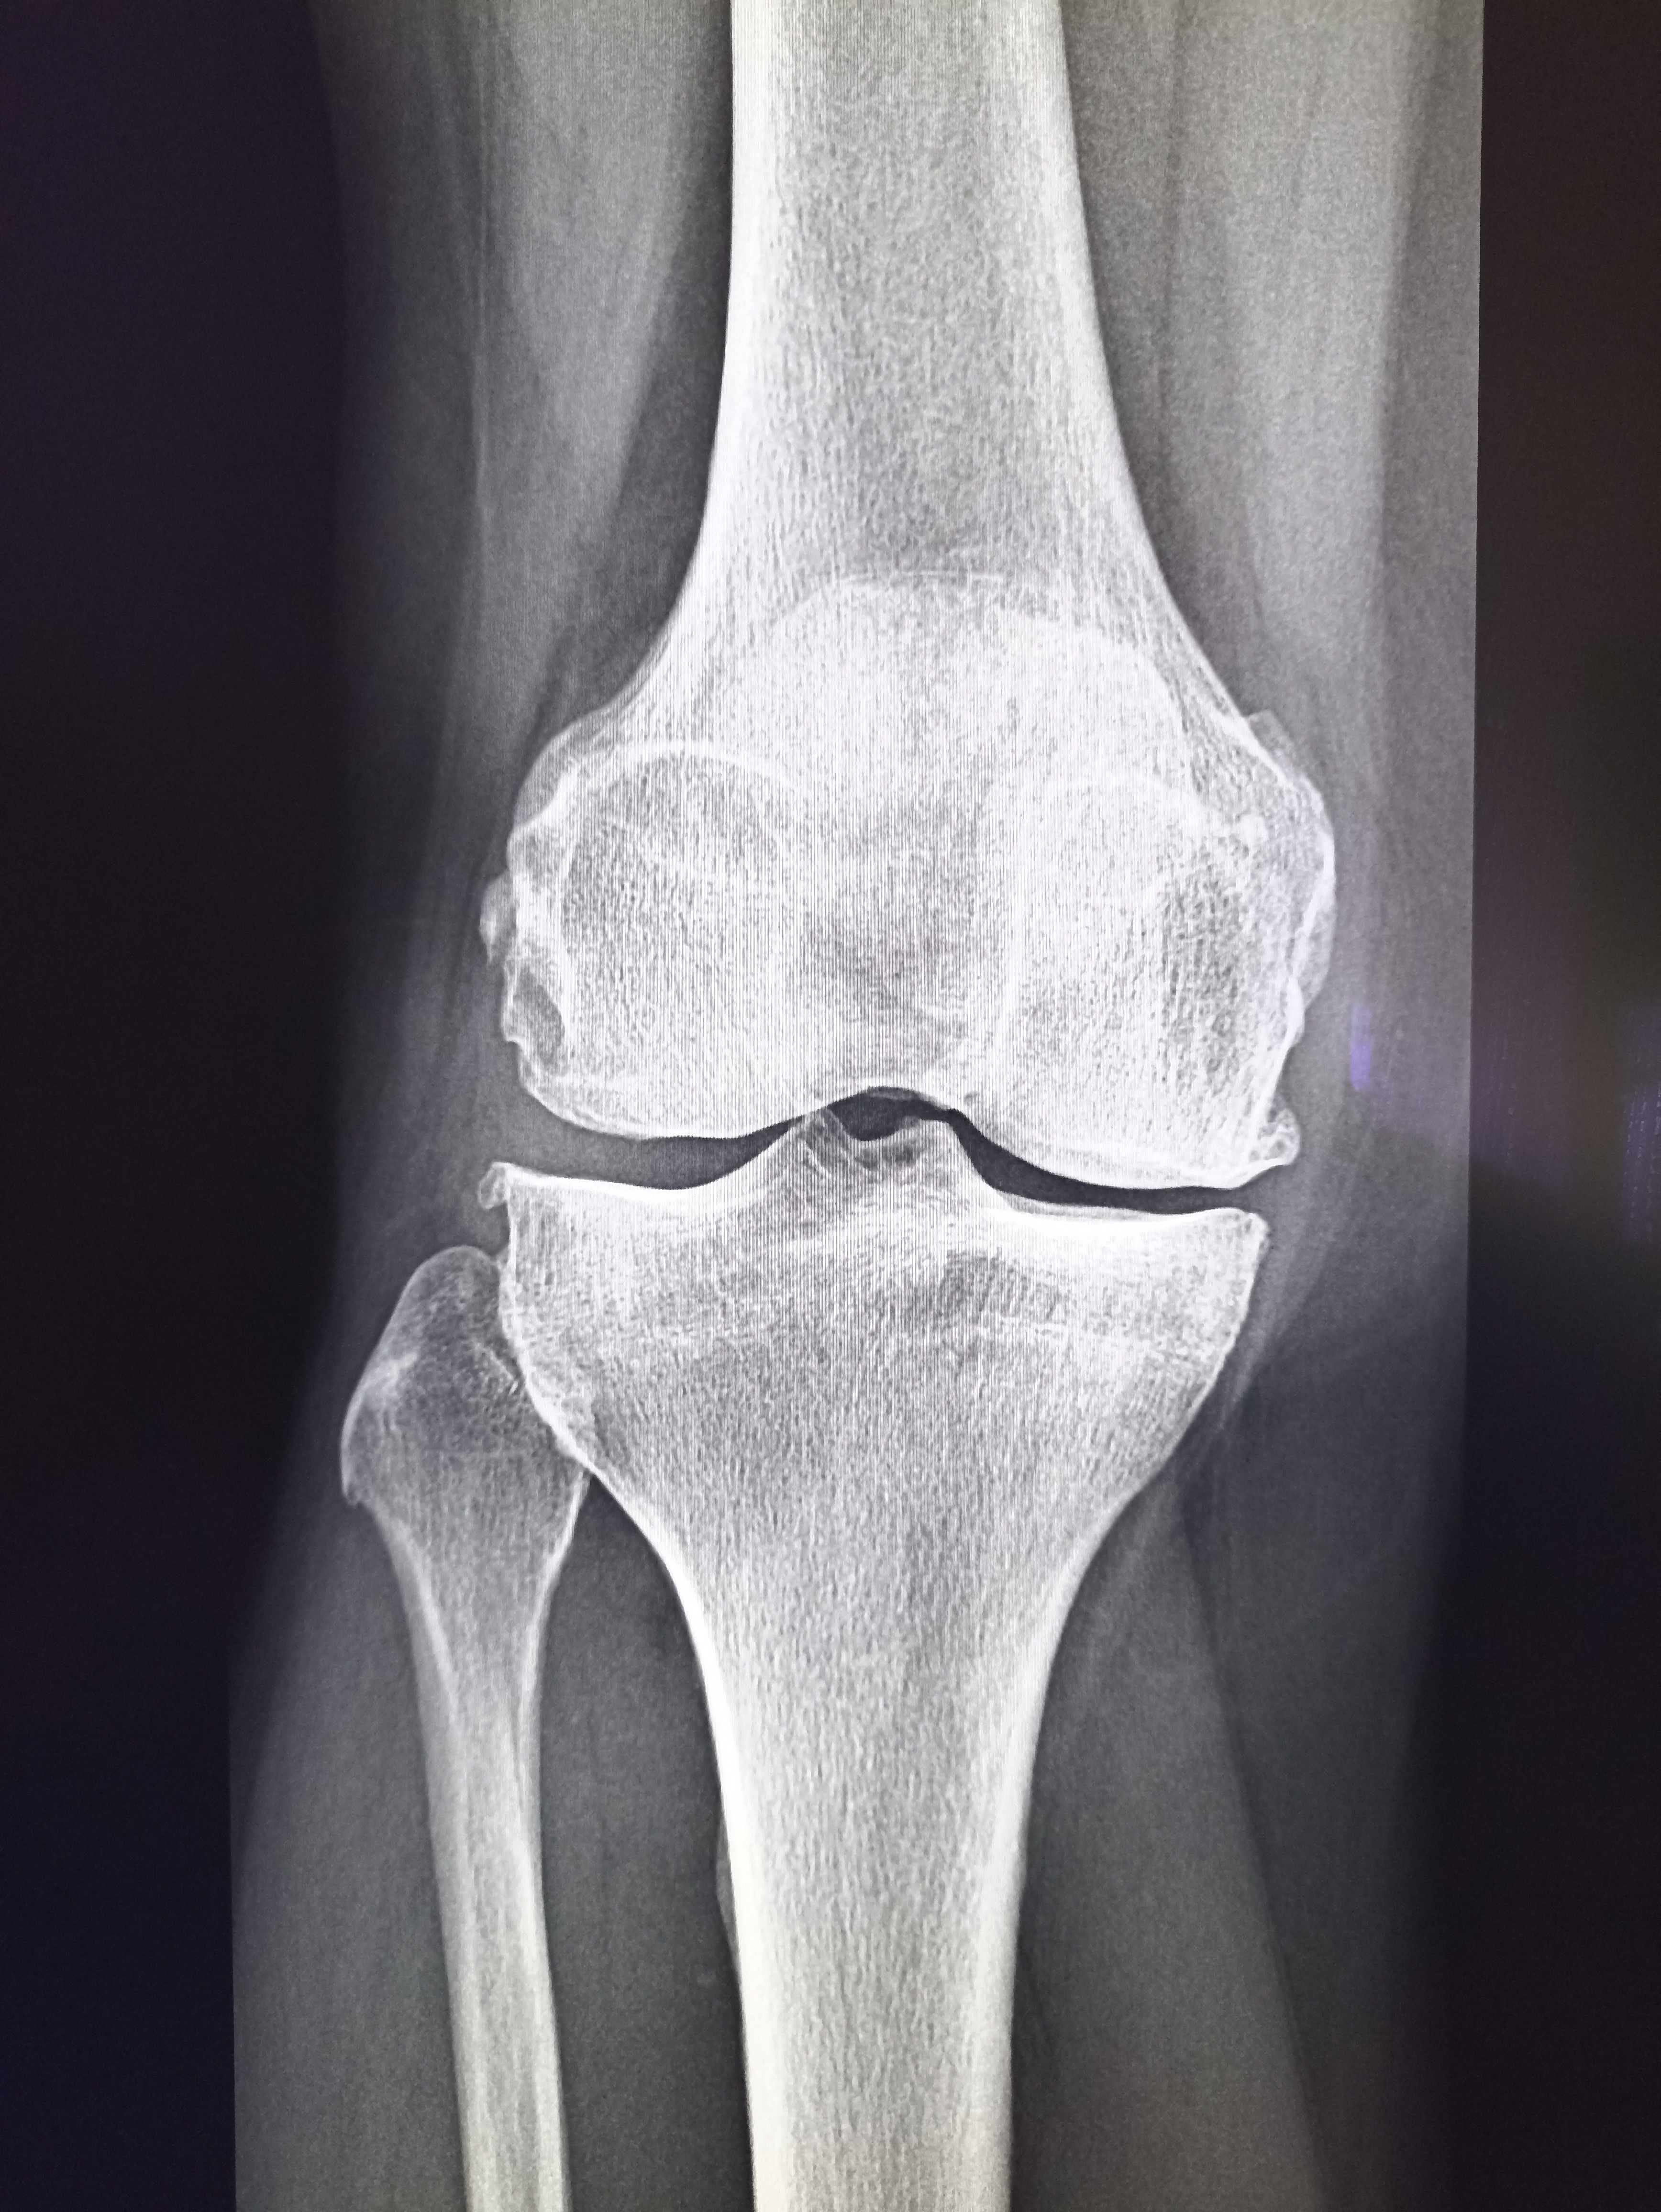

Здравствуй двачик, на прошлой неделе вышел из отпуска и уже дергается глазик, вчера сидел на работке пока поликлинику не закрыли и не все доделал. Не могу перестать кричать внутри головы! Потому мы с вами будем сегодня играть в доктора! Я буду вам показывать фоточки а вы угадывать пиздецомы! Што шпогнали! Найдите поломку!